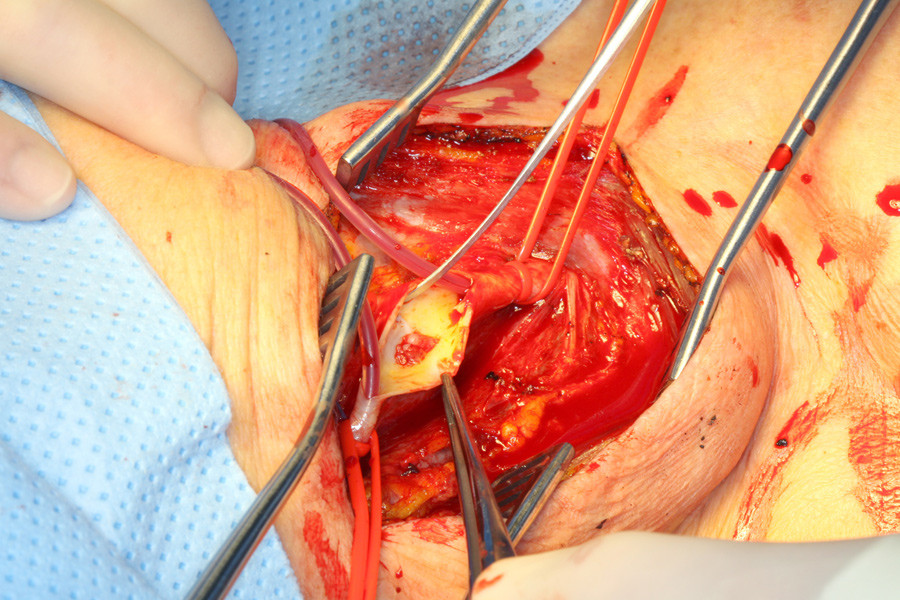

Det ble gjort carotiskirurgi med ekstirpasjon av en gelatinøs stilket, fluktuerende masse (bilde kun i nettutgaven), som ved mikroskopisk undersøkelse var dominert av fibroblaster, ikke lipider eller kalk som ved aterosklerotiske plakk. Flere måneder postoperativt er pasienten fri for nye iskemiske hendelser.

Høyst trolig var den veggfaste tumoren i høyre a. carotis interna årsak til de iskemiske hendelsene. Tumoren er sannsynligvis stadig blitt fragmentert og har embolisert til hjernen, hvorpå det ikke ble påvist noe patologisk ved ultralyd og CT-angiografi. Under de nakkekirurgiske inngrepene kan det ha oppstått skade (disseksjon) av arterien, med utvikling av et trombogent fokus på indre vegg og endrede anatomiske forhold i nakken, noe som har resultert i mobil arterie som sekvele (1). Skade av a. carotis interna ved nakkekirurgi er en velkjent, men uvanlig komplikasjon. Mobiliteten i karet, med leiendring sett på CT-angiografi, kan i tillegg gi skade i indre karvegg, med trombogen flate som følge.